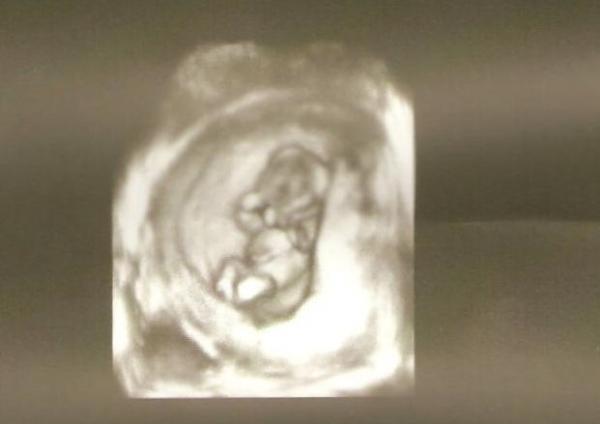

Dodane przez: Misiaczek Opis zdjęcia: 3.5 miesiaca;) maluiszek Podziel się ze znajomymi! Skopiuj i prześlij poniższy link: URL: |

Wzruszają mnie takie fotki:)